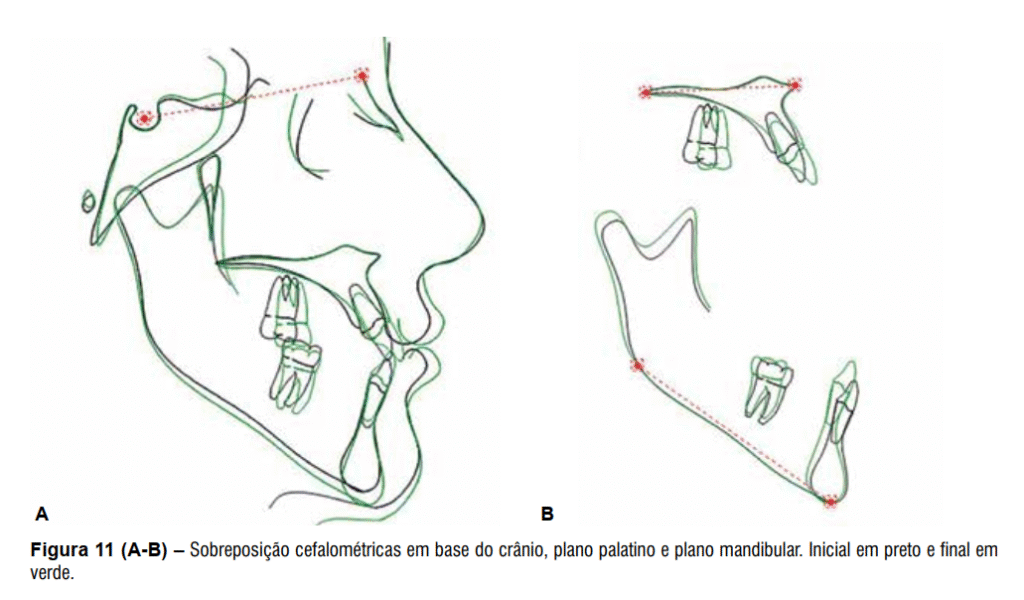

Após a remoção do aparelho fixo foi instalada como contenção uma placa de Hawley superior, 3×3 inferior e uso noturno de mentoneira com finalidade de restringir o crescimento mandibular. O tratamento proposto possibilitou a correção da discrepância transversal e da relação anteroposterior de forma satisfatória, melhorando o perímetro do arco e obtendo-se uma relação molar de Classe I (Figura 8 A-E), além da melhora significativa do perfil facial e estética mais agradável (Figura 9 A-B). As telerradiografias inicial e final mostram a melhora da relação entre as bases ósseas (Figura 10) juntamente com a sobreposição dos cefalogramas (Figura 11).

O componente esquelético da maxila não apresentou grandes alterações, entretanto, a mandíbula teve significante crescimento representado pela variável CoGn. Também houve suave aumento das variáveis que representam o padrão da face no sentido vertical, com destaque para a alteração sofrida pela variável AFAI, que teve aumento de 4,1 mm (Tabela 1).

Os efeitos dessa mecânica em duas fases, quando comparado à mecânica ortodôntica realizada em uma fase somente, estão baseados no fato de que o avanço da maxila pelo uso da máscara de Petit promove a melhora no posicionamento dos incisivos, principalmente no arco superior, o que pode ser verificado quando se observa a protrusão e inclinação para vestibular dos incisivos superiores e a mesialização e angulação mesial sofrida pelos molares superiores por meio da mecânica ortodôntica realizada pela protração da maxila¹³⁻²² (Tabela 1). Além disso, outro fator que reforça a escolha desta mecânica em duas fases é que a utilização da protração maxilar no tratamento de má oclusão de Classe III tem alcançado merecido destaque na última década, muito em decorrência dos resultados favoráveis e em um período relativamente curto de tratamento (4 a 9 meses de fase ortopédica)3,15.

No caso apresentado nesse trabalho, as alterações esqueléticas ocorreram em menor proporção quando comparadas às alterações dentoalveolares (Tabela 1). Entretanto, estima-se que a associação dessas alterações favorece a correção da discrepância anteroposterior, assim como a harmonia da face e consequente estética do sorriso. A aplicação do protocolo em duas fases em uma paciente pós-pico de crescimento pode gerar efeitos esqueléticos no sentido de minimizar a discrepância anteroposterior existente ao início do tratamento, principalmente se o tratamento se iniciar no início ou logo após o surto de crescimento pubera¹³.

O aumento da altura facial anterior inferior (AFAI) é outro efeito da mecânica aplicada ao tratamento e que colabora para atratividade da face. Os registros cefalométricos inicial e final do paciente mostram para um aumento de 4,1 mm (Tabela 1) da AFAI durante o tratamento. O aumento da AFAI promove uma rotação da mandíbula no sentido horário, diminuindo a projeção do mento e favorecendo a estética da face para o paciente Classe III esquelética¹¹ (Figura 11). Apesar dos

efeitos favoráveis obtidos pela mecânica ortodôntica no presente caso clínico, um controle no desenvolvimento vertical dos dentes posterossuperiores poderia ter sido inserido mediante a instalação do aparelho expansor modificado por McNamara, o qual apresenta recobrimento oclusal em acrílico dos dentes posteriores e visa minimizar a rotação da mandíbula no sentido

horário e aumento da AFAI¹.